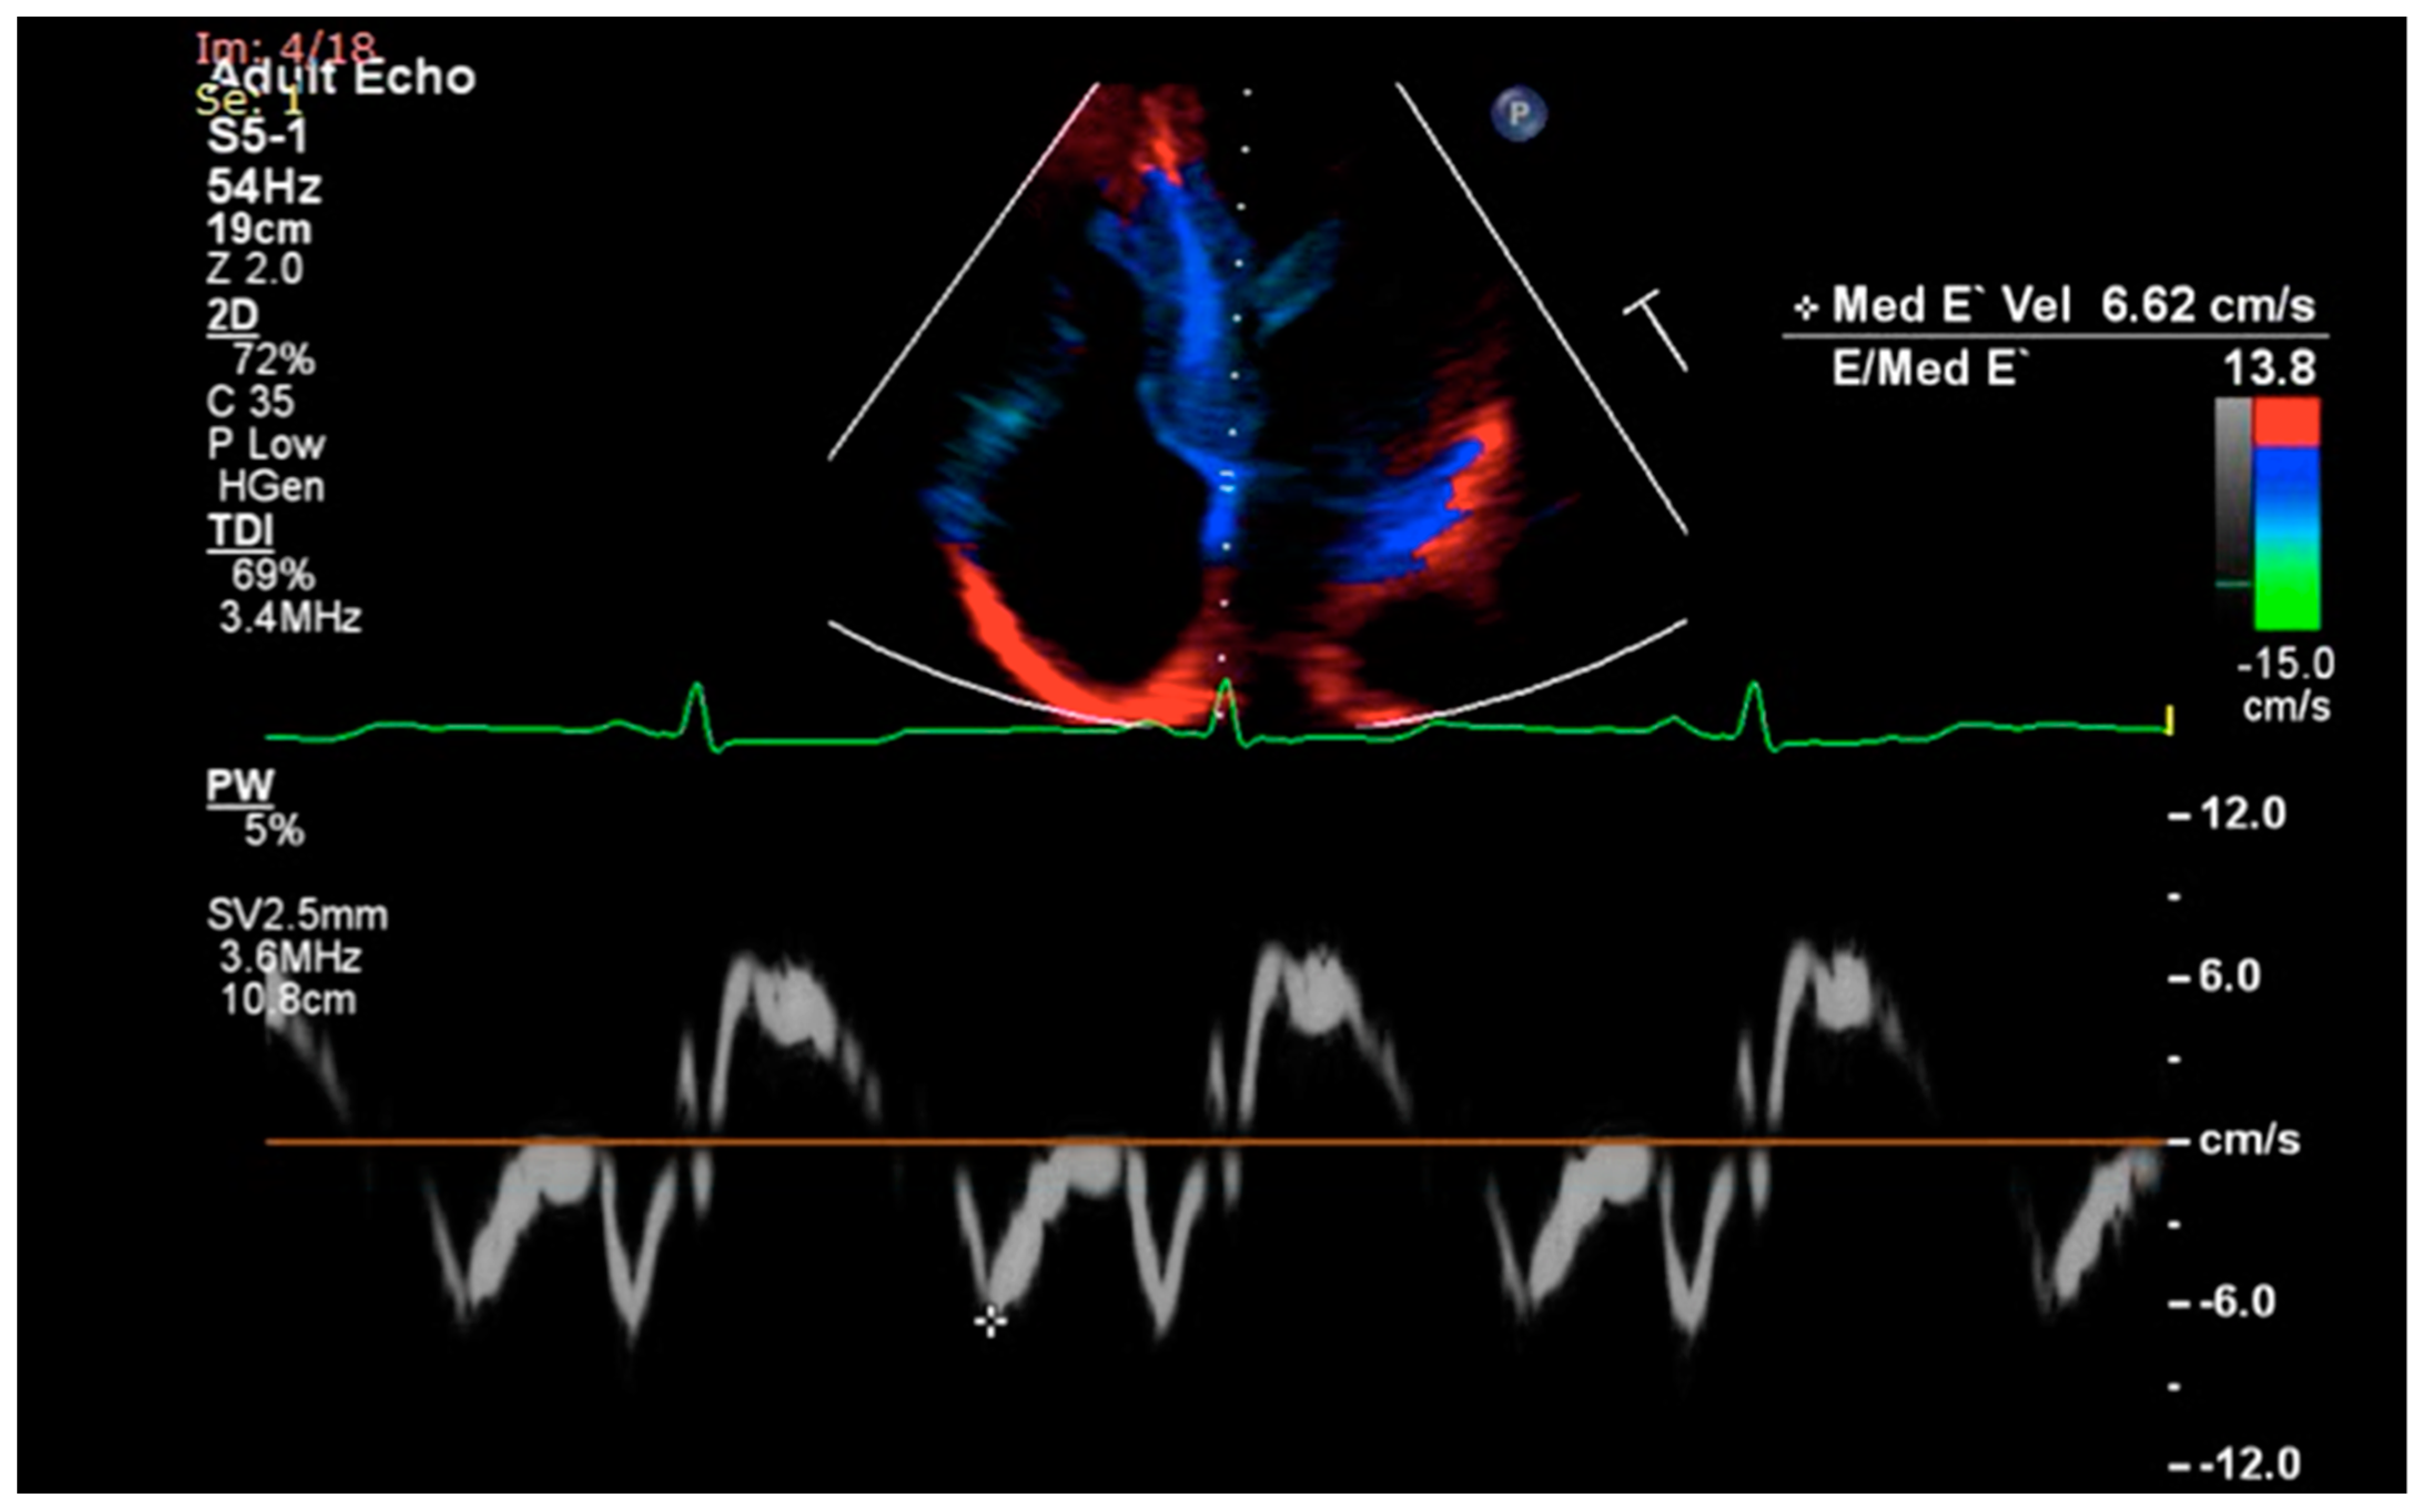

2.2. Diastolic Dysfunction

2.2.1. Diastolic Dysfunction in Amyloidosis

2.2.2. Diastolic Dysfunction in Sarcoidosis and Hemochromatosis